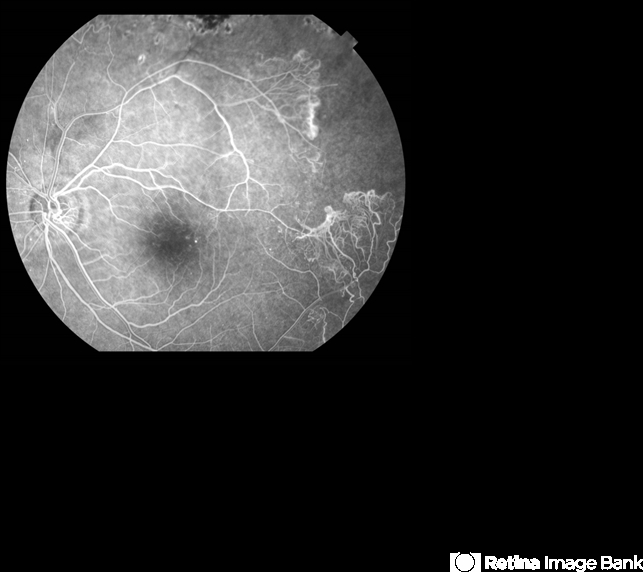

- sickle cell retinopathy, sea fan

- Fluorescein angiography (early phase) of a 40-year-old man with African heritage and sickle SC disease. Sea fans are present temporal to the macula.